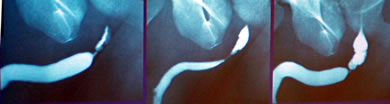

Медицинские исследования: уретрография и цистография